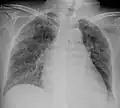

Chest X ray showing miliary tuberculosis

Miliary tuberculosis is a form of tuberculosis that is characterized by a wide dissemination into the human body and by the tiny size of the lesions (1–5 mm). Its name comes from a distinctive pattern seen on a chest radiograph of many tiny spots distributed throughout the lung fields with the appearance similar to millet seeds—thus the term "miliary" tuberculosis. Miliary TB may infect any number of organs, including the lungs, liver, and spleen.[2] Miliary tuberculosis is present in about 2% of all reported cases of tuberculosis and accounts for up to 20% of all extra-pulmonary tuberculosis cases.[3]